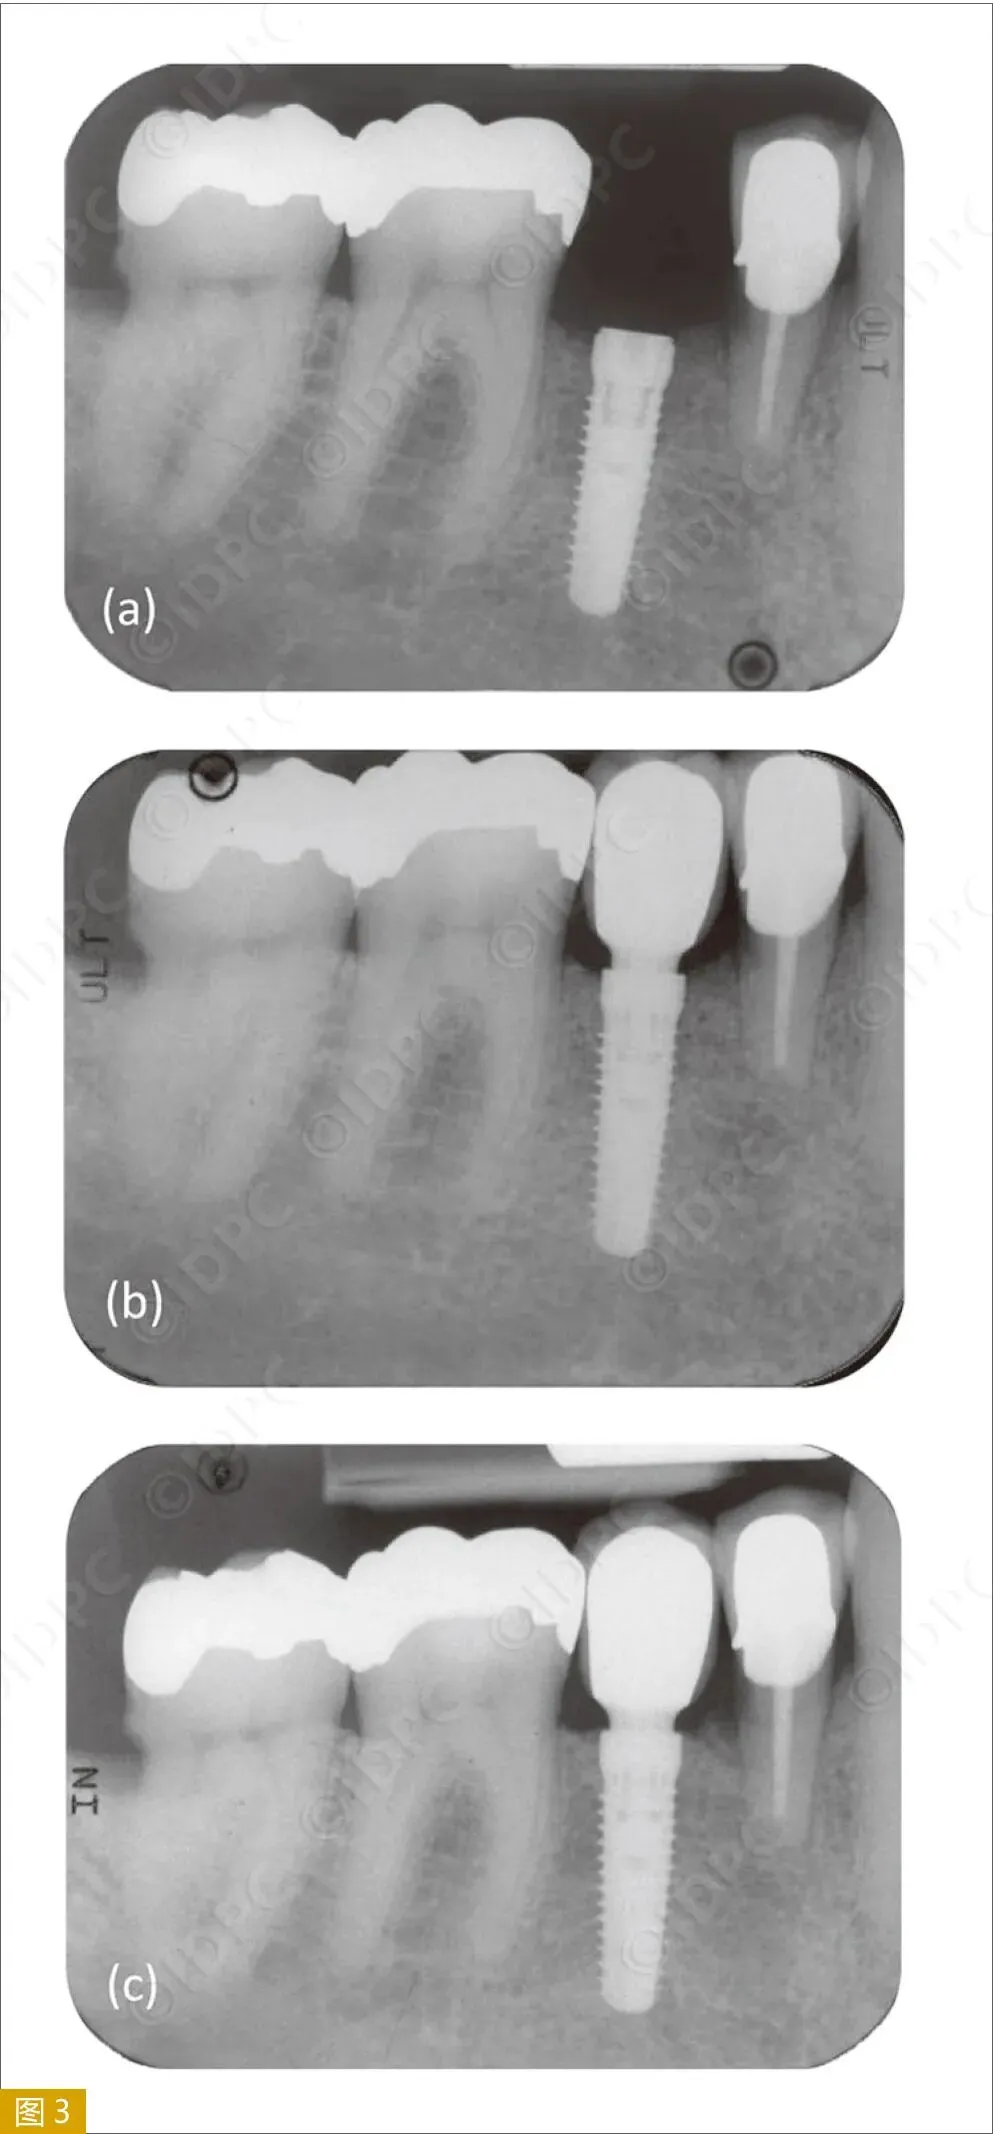

表3显示了从种植体植入到负重后5年的平均骨水平变化。从手术到负重,可明显观察到种植体周围骨重建,平均值为−0.52±0.55mm。从负重到5年随访,平均骨水平变化保持稳定(−0.09±0.43mm)(图3)。

图3:种植体周围骨水平变化的标准根尖片:(a)种植体植入后;(b)载荷后(基台、冠戴入后);(c)载荷5年后。

将载荷5年后的结果分为三组:15.1%的种植体周围有明显骨增加,61.6%的种植体骨水平变化无临床意义(±0.25mm),23.3%种植体发生骨丧失(>0.25mm)。

很多文献均有记录边缘骨水平变化。报道显示,骨重建发生在手术和载荷之间。研究中所记录的变化大体在0.5 mm左右,但在随机或观察性试验中可以达到1mm以上。本研究记录的骨重建变化为−0.52±0.55 mm,与其他研究结果相符。近45%的种植体为骨水平植入。这与种植体肩部水平的边缘骨重建有关,可能是初始边缘骨丧失的一个原因。从载荷到5年后随访,种植体肩部水平的边缘骨显示临床稳定(−0.09±0.43mm)。76.7%的种植体在载荷到载荷5年后显示骨水平稳定或发生骨增加。共有23.3%的种植体发生骨丧失(12.8%的种植体骨丧失>0.5 mm)。Donati等人的临床随机试验显示,52%的种植体在5年观察期间出现骨增加,与本研究的骨增加结果相符。这些结果也符合Messias等人和Ioannidis等人的临床对照研究结果,以及Wennström等人的临床研究结果。此外,本研究结果与Moergel等人发表的同种植系统的第一年初步试验结果相符。多个研究报告显示,种植体的平台转移设计可能有助于骨稳定。